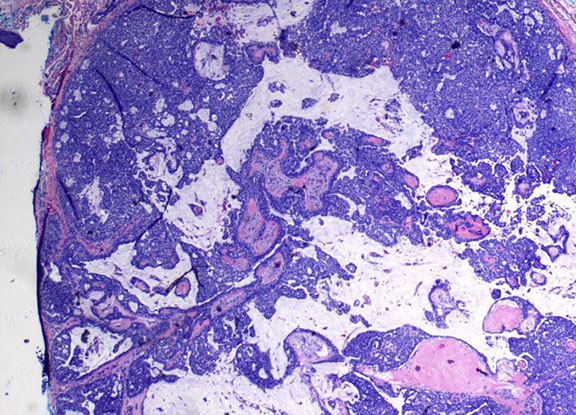

Pilomatrixoma

Trichohyaline granule (which are usually seen in hair shafts) in a pilomatrixoma

- aka calcifying epithelioma of Malherbe

solitary, bluish, firm (often calcifies), benign subepidermal spherical nodule

b9 hair follicle tumor

MC on face of kids or young adults

- 75% of childhood adnexal tumors

- can have multiple lesions in myotonic dystrophy

Sharply circumscribed cyst-like structure in dermis, possibly contiguous with hair follicle (may arise from hair matrix)

- can have inc mits (the malignant form is rare and usually very atypical)

- may have trichohyaline granules (which are usually seen in hair shafts)

3 cell types in fragmented cyst wall:

1) outer layer of blue (basophilic) basaloid martical cells with round nuclei and scant cytoplasm which dies and become dead keratin, which are the ghost cells

- imitate the cells in the root, or bulb of a normal hair follicle

2) mixed zone of eosinophilic cells c large round vesiculated nuclei

3) central zone sheets of keratinized pink "ghost" or "shadow" cells c distinct cell borders and central unstained nuclei

- difference from BCC: basaloid cells undergo abrupt keratinization and form "ghost" cells

Has foci of foreign body reaction, calcifications and ossification in shadow cell lobules

See melanin in shadow cells

Fibrotic stroma infiltrated with granulomatous inflam

Solid nests of basaloid cells may cause misdiagnosis of BCC

Ddx: Basal cell carcinoma c matrical differentiation (differs by continuity with epidermis and abrupt transition into shadow cells without the eosinophilic zone)